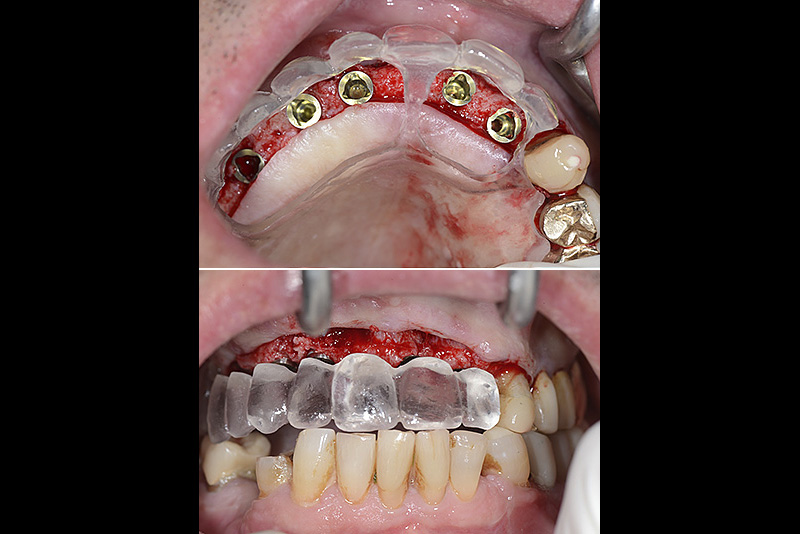

Vengono utilizzati 2 tipi di provvisori: il primo, cementato ai denti vicini, viene utilizzato dal momento dell’estrazione del dente fino ad impianto osteointegrato (circa 6 mesi); il secondo, avvitato direttamente all’impianto, ha una funzione di prova estetica ma soprattutto di guida per la maturazione dei tessuti gengivali peri-implantari portandoli verso la maturazione completa prima di posizionare la corona finale in disilicato di litio.